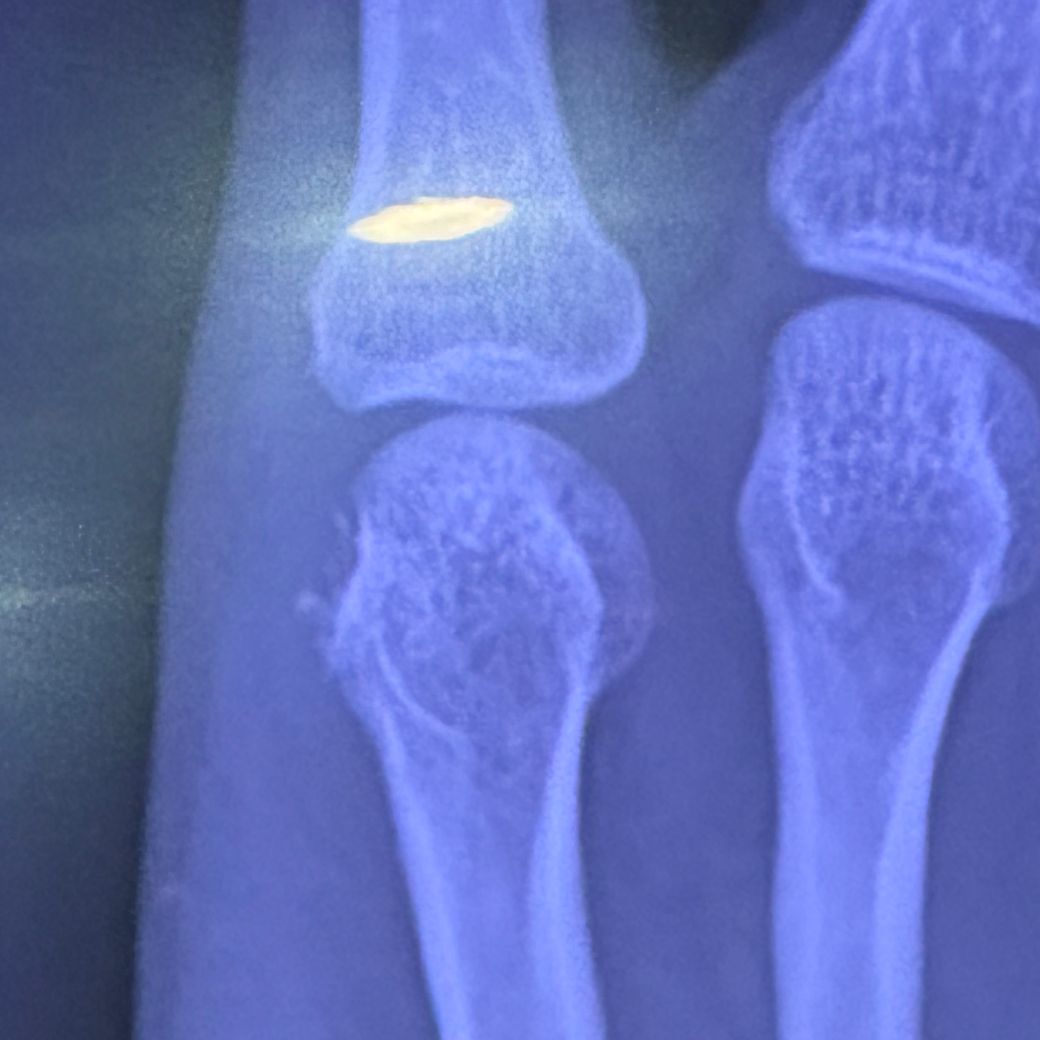

갑자기 새끼손가락 마지막 관절에 통증이 있어 xray찍으니 뼈가 녹은거 같다고 mri찍어보라네요

왼쪽이 뼈가 이상하다는 부분입니다

• 1번 째 사진